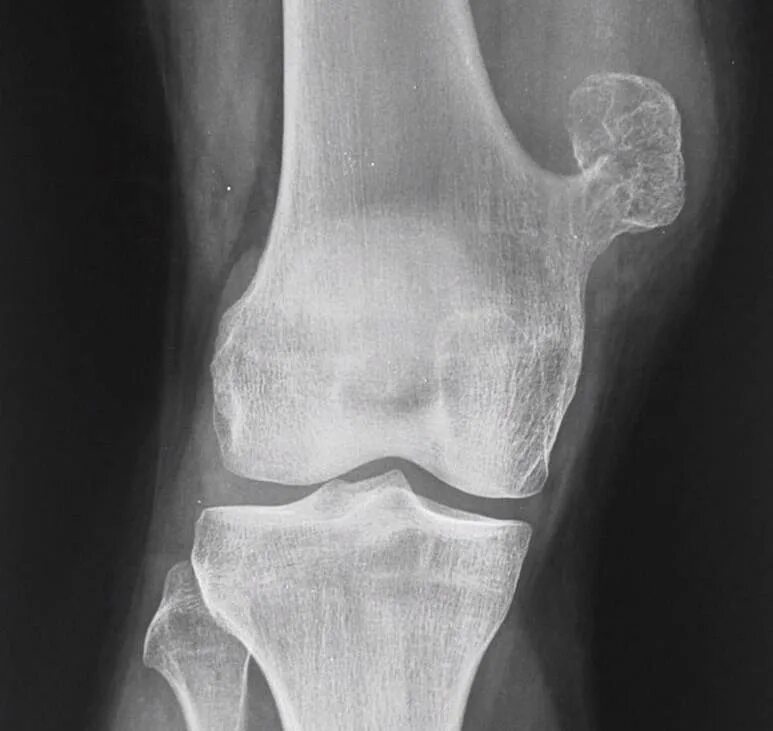

Экзостоз мкб 10